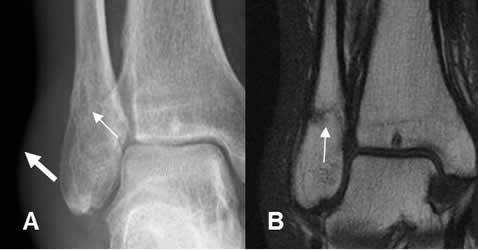

Fig 37. Fractura oblicua-transversa.

A: Rx tobillo AP y B: RM corte coronal. Fractura no desplazada del maléolo externo (Flecha delgada), con edema de tejidos blandos. (Flecha gruesa).